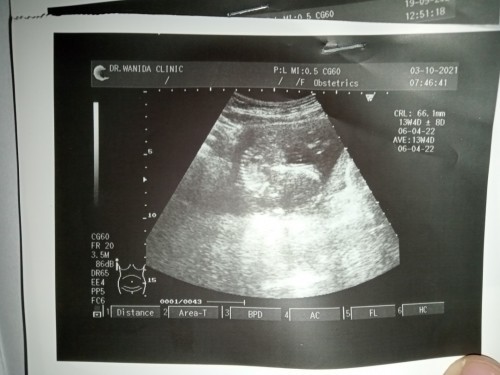

คือเมื่อวานไปคลินิกมา หมอบอกหัวใจลูกเต้นปกติดี ลูกตัวเล็กไปมั้ยคะ ตอนนี้ท้องได้16+3วีคแล้ว #ขอคำแนะนำหน่อยค่ะ